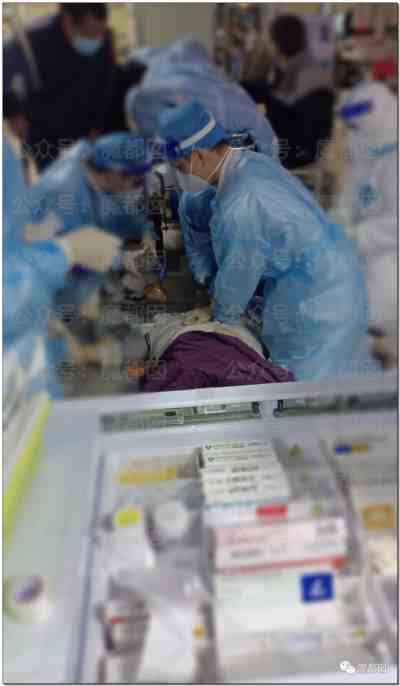

第六、现在医护真的有那么忙吗?是真的!

我们已经贴了不知道多少了,现在最苦最累的就是医护们,拼死拼活的抢救,所以请大家多给他们一点容忍和理解!